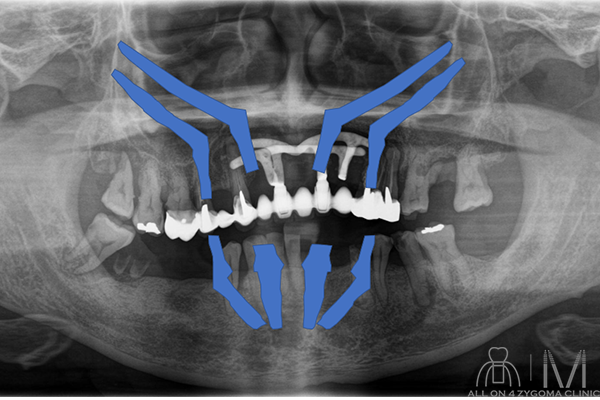

術前パノラマ画像所見

42┴137、65┬27が欠損。└7、7┬13…続きを読む

42┴137、65┬27が欠損。└7、7┬13が残根。上顎前歯部の1┴2部にブレードインプラントを認め、天然歯とBrで繋いだ様な所見を認める。下顎は著明な骨硬化を認める。└57、7┬35の根尖相当部には嚢胞様所見を認める。